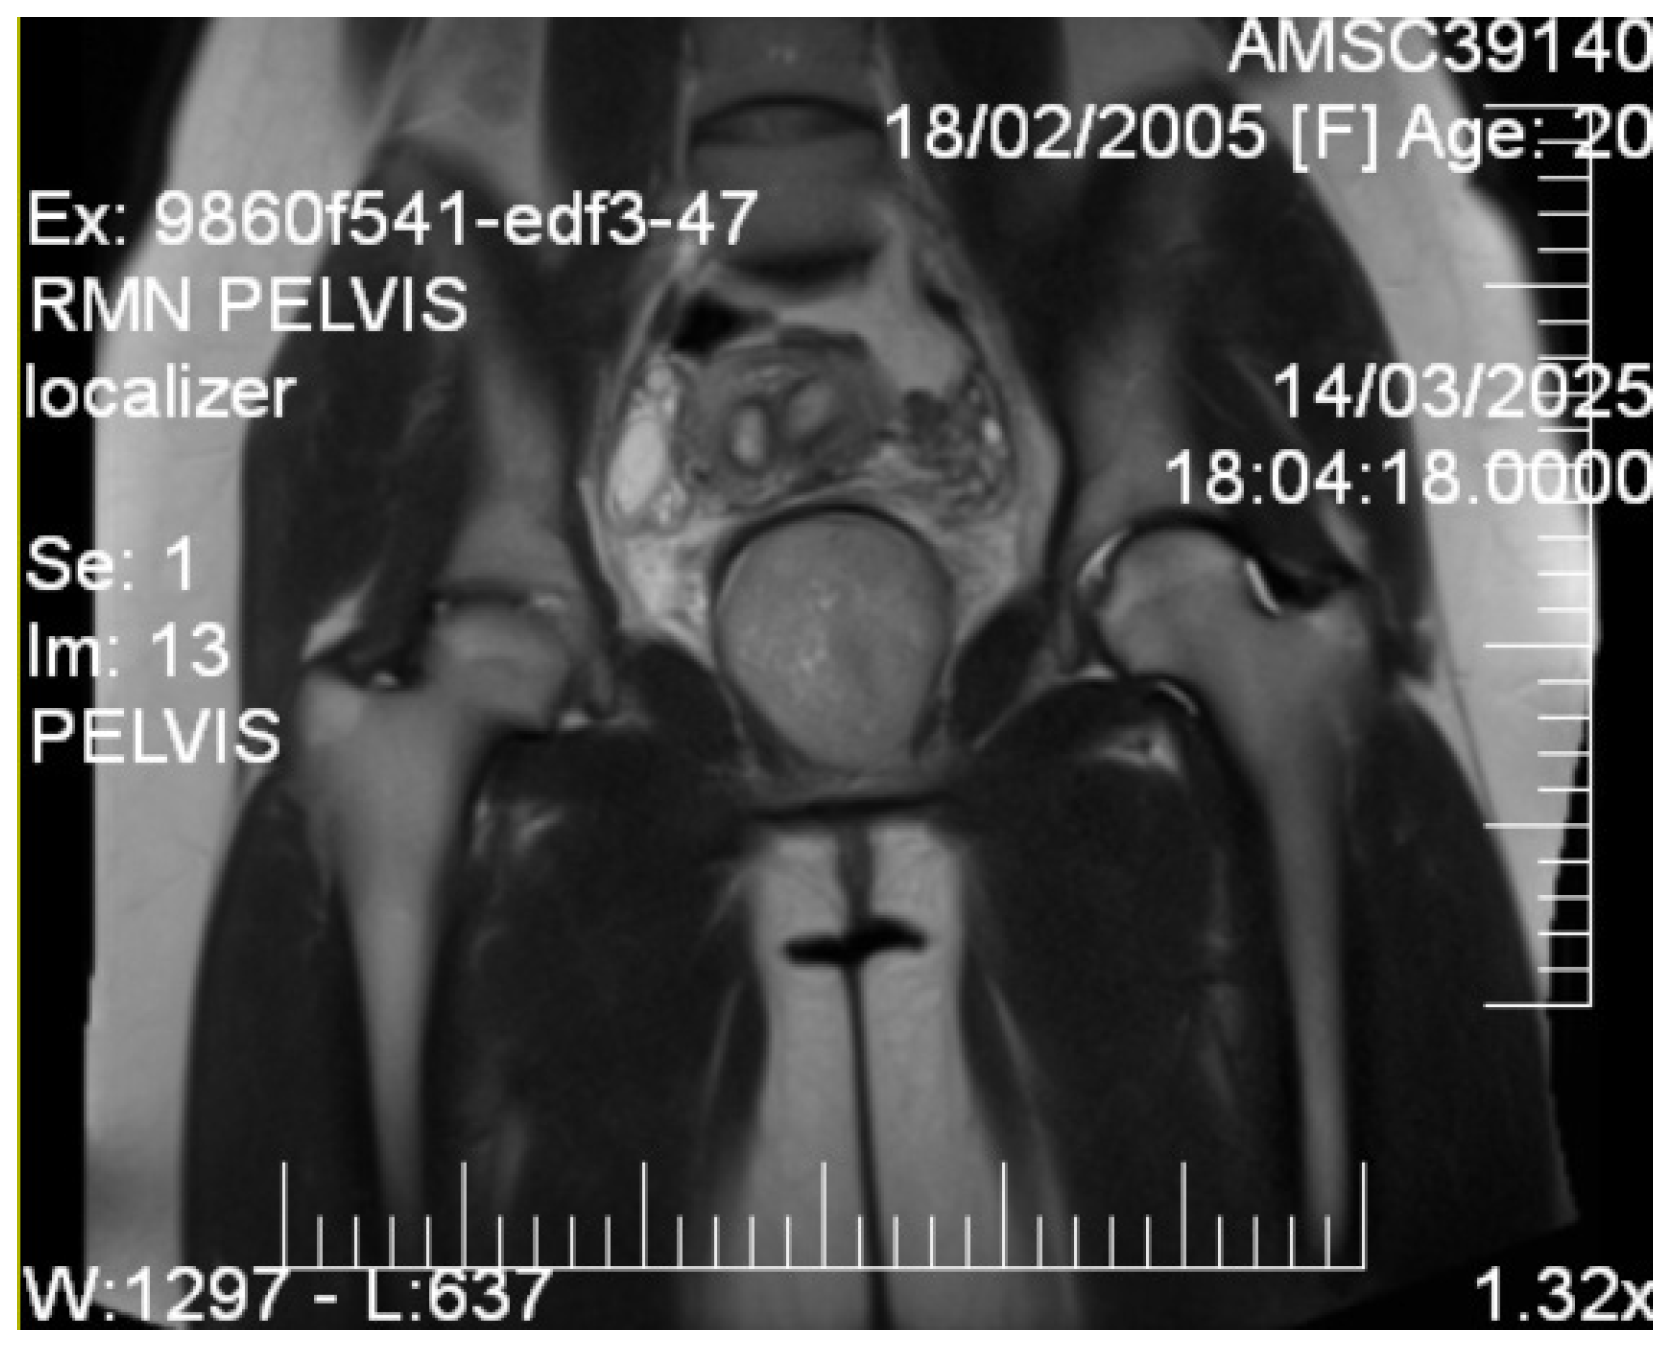

Given the patient’s young age and solid mass characteristics raising concern about malignancy, comprehensive magnetic resonance imaging (MRI) was performed using a 1.5-Tesla scanner with multiplanar sequences (General Electric, Cluj-Napoca, Romania). The MRI demonstrated signal intensity patterns highly suggestive of leiomyoma: isointense to muscle on T1-weighted imaging, markedly hypointense on T2-weighted imaging (characteristic of leiomyoma due to high fibrous content), restricted diffusion with high ADC values of 0.9 × 10−3 mm2/s (b-values: 0, 1000 s/mm2) consistent with benign leiomyoma, and homogeneous enhancement following gadolinium administration. In the literature [12], benign leiomyomas typically demonstrate ADC values in the range of 0.8–1.2 × 10−3 mm2/s, atypical leiomyomas may overlap, but are often slightly lower (0.7–1.0 × 10−3 mm2/s), while leiomyosarcomas tend to show more pronounced restriction, often <0.8 × 10−3 mm2/s. These ranges overlap, highlighting that although MRI provides highly suggestive features, histopathological confirmation remains essential. MRI also confirmed the septate uterus and showed detailed anatomical relationships (Figure 3 and Figure 4).

Coronal T2-weighted pelvic MRI. The image shows a well-circumscribed, T2-hypointense solid mass located in the vesicovaginal space (6.9 cm), displacing adjacent pelvic anatomy. The bladder is displaced anteriorly, the vagina posteriorly, while the rectum and bowel are visualized further posteriorly. Gluteal and pelvic floor musculature are partially delineated laterally. These features are consistent with a leiomyoma.